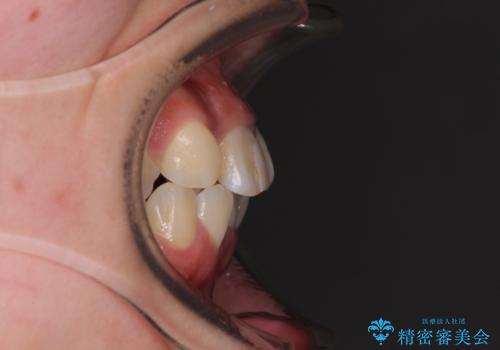

- 放置した虫歯や抜いたままの奥歯、前歯のデコボコを気にして来院された患者様です。

口元の突出感は少なく、下顎の叢生は軽微なものであったので、叢生の強い上顎左右の小臼歯を1本ずつ抜歯し、ワイヤー装置にて矯正治療を行うこととしました。